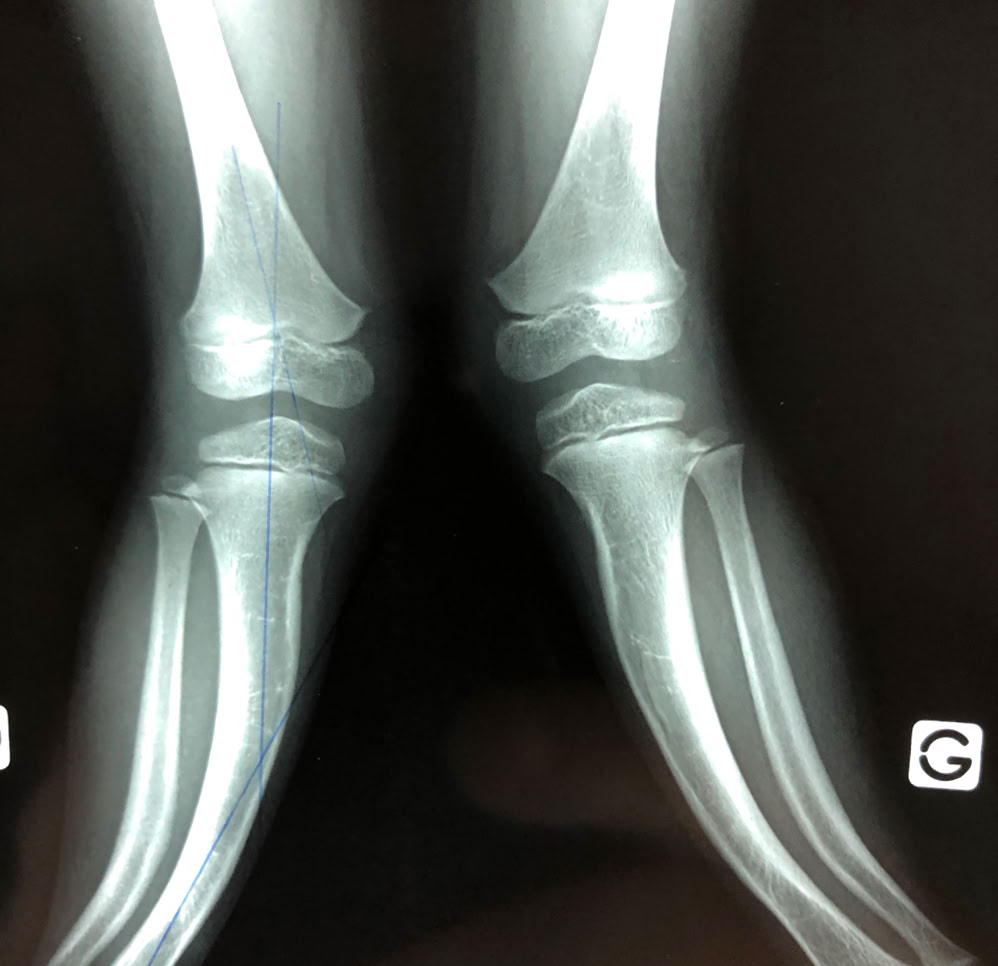

Esta preciosidad, es Ornella, víctima de malos tratos por parte de su padre, por el simple hecho de tener las piernas torcidas. Le hemos hecho una osteotomía de tibia para alinear su pierna izquierda. El bocadillo y los caramelos que le daba el Dr. Epeldegui le sentaron de maravilla.